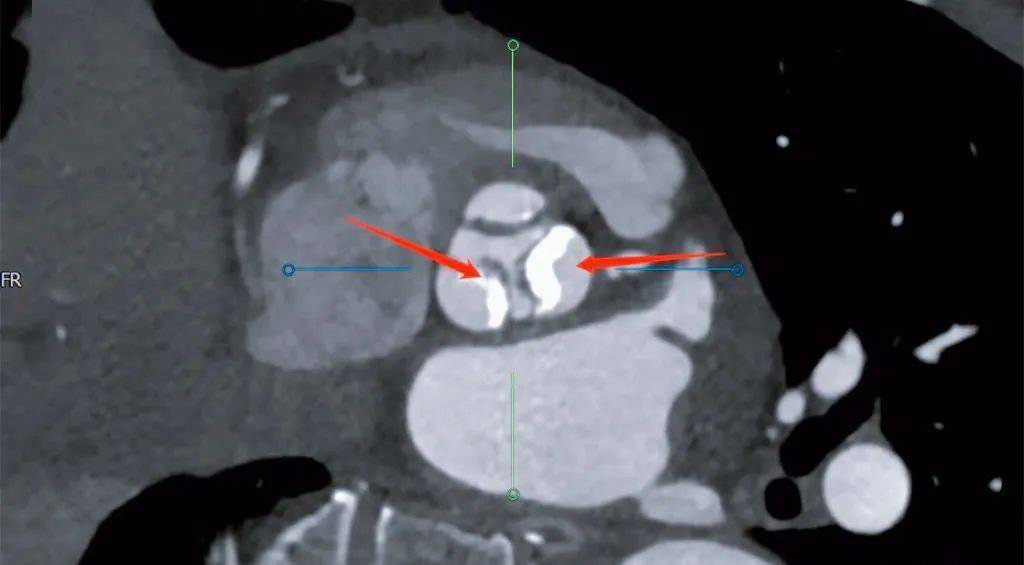

主动脉瓣严重狭窄、瓣叶钙化

摆在心脏大血管团队面前有几项难题:一是患者的主动脉瓣叶钙化非常严重且分布不均,二是患者呈现恶液质终末衰竭状态,三是患者长期卧床后腿部关节僵硬弯曲,无法伸直。